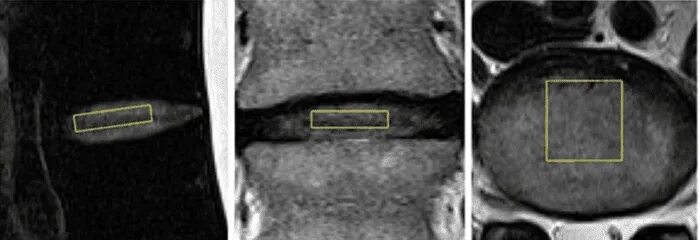

Мрт признаки дегенеративных изменений